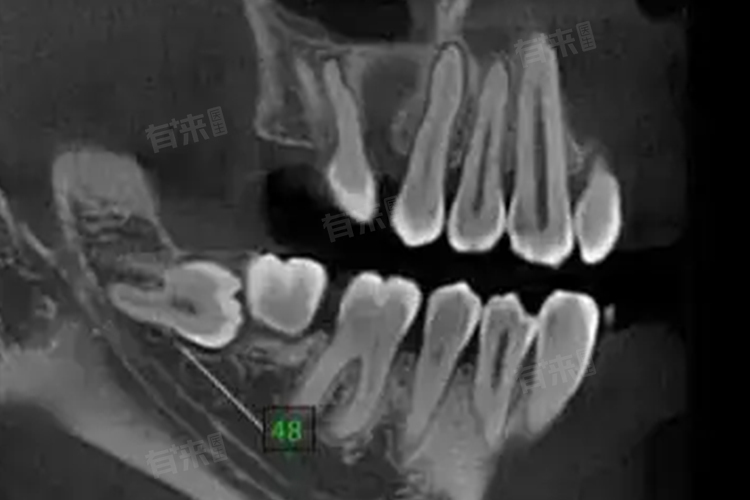

- 确定智齿位置:智齿的生长位置多种多样,有的正常萌出,有的可能倾斜、水平甚至倒置生长。通过拍片子,如口腔全景片或口腔CT,可以清晰地看到智齿在牙槽骨中的具体位置,为医生制定拔牙方案提供准确依据。

- 评估与邻牙关系:片子可以显示智齿与周围邻牙的紧密程度,如果智齿与邻牙靠得太近,在拔除过程中可能会对邻牙造成损伤。通过片子提前知晓这种情况,医生在操作时可以更加小心谨慎,采取相应的保护措施。

- 查看牙槽骨情况:了解智齿周围牙槽骨的密度、厚度等情况,对于拔牙的难度评估至关重要。如果牙槽骨过于坚硬,可能需要使用更强大的器械和力量来拔除智齿,这也意味着拔牙过程中的风险可能会增加。

- 观察周围神经血管:口腔内存在着丰富的神经和血管,尤其是下牙槽神经。通过片子可以判断智齿与这些重要结构的距离,避免在拔牙过程中损伤神经血管。一旦损伤下牙槽神经,可能会导致下唇麻木等严重后果。